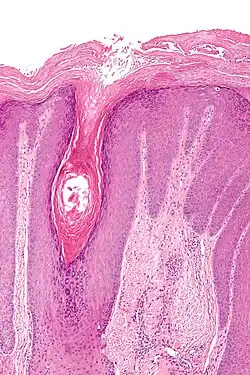

Le diagnostic repose d'une part sur les symptômes ( prurit , lichénification et évolution chronique ) et d'autre part sur l' histologie .Dans le cadre d'une biopsie, un échantillon de tissu est prélevé dans la zone modifiée et examiné histologiquement. Le lichen simplex chronicus peut être diagnostiqué de manière fiable de cette manière. Les diagnostics différentiels possibles doivent être envisagés à l'avance (dermatite de contact , dermatite atopique ou lichen plan)[3] .